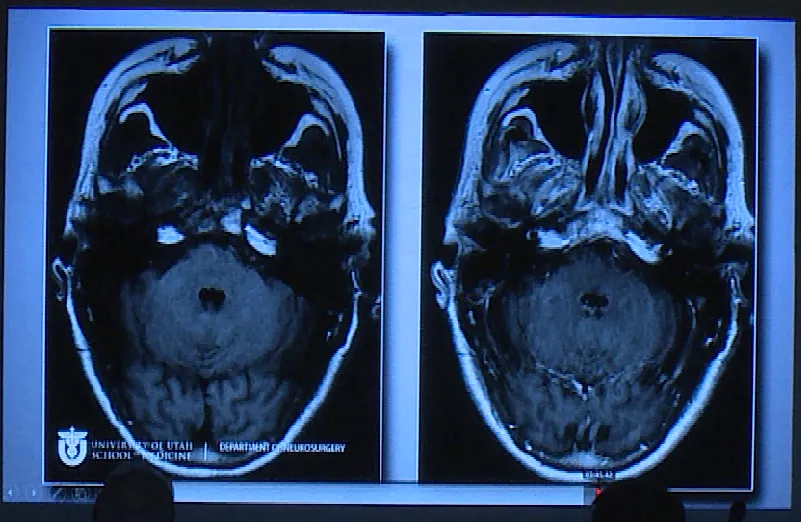

一位62岁女性患者,与垂体瘤抗争长达35年,曾因垂体瘤复发接受放射治疗。此次因出现复视症状随访,发现已经发展巨大的垂体瘤。

进行开颅手术,术后影像片子显示肿瘤切除干净。

Couldwell教授演讲中展示的部分巨大垂体瘤